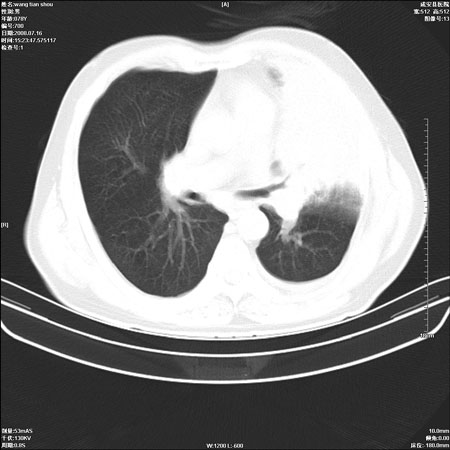

以下是引用qingjing在2008-7-16 19:55:00的发言:[br]1、左上肺不张并堵塞性炎症,建议支气管镜详查;[br]2、左侧胸腔少量积液。

以下是引用zsl6918在2008-7-17 8:09:00的发言:[br]肺炎胸膜炎可能性大,建议抗炎治疗后复查

以下是引用wzr在2008-7-16 20:26:00的发言:[br]左肺肺不张伴阻塞性肺炎!另:左侧胸腔少量积液。建议纤支镜检查!